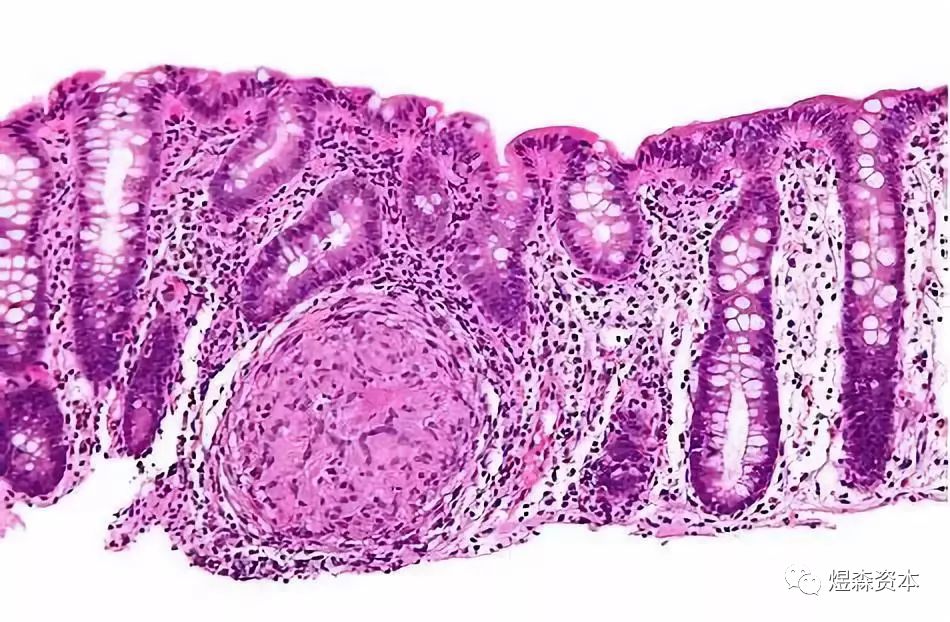

在这项研究中,研究人员回顾了收集的440例结直肠癌病人样本,并通过一种荧光PCR方法进行检测,根据随访数据和就医记录对一线化疗药物和PIK3CA突变的相关性进行了评估。利用结直肠癌肿瘤和细胞研究了PIK3CA突变在化疗抵抗中可能发挥的作用。

研究人员发现PIK3CA基因在结直肠癌病人中的突变比例大约为9.55%,与TNM阶段和病理分级存在相关性。携带PIK3CA突变的结直肠癌病人对一线化疗药物的应答情况比不携带该基因突变的病人更差。PIK3CA突变的肿瘤细胞对一线化疗药物的敏感性也更差。研究表明PIK3CA突变能够通过诱导PI3K/Akt信号途径的激活增强LGR5+结直肠癌干细胞的存活和增殖能力,导致化疗抵抗的产生。

这些结果表明PIK3CA突变能够诱导PI3K/Akt激活促进结直肠癌干细胞的存活和增殖,导致细胞抵抗化疗药物。PIK3CA mutation/LGR5+的表达或可用来检测结直肠癌病人的化疗抵抗情况。